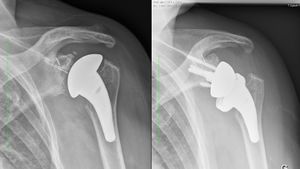

Reverse shoulder arthroplasty is a more reliable treatment than hemiarthroplasty for complex proximal humerus fractures at least in elderly patients because its functional outcomes appear to depend less on tuberosity healing and rotator cuff integrity (Figure).[90]

Reverse shoulder athroplasty for fracture. Frontal, axial and lateral Lamy radiographs after a reverse total shoulder implant. Note the lower positioning of the glenoid baseplate, the satisfactory reconstruction of the tuberosities, and the absence of cement at the autograft level.